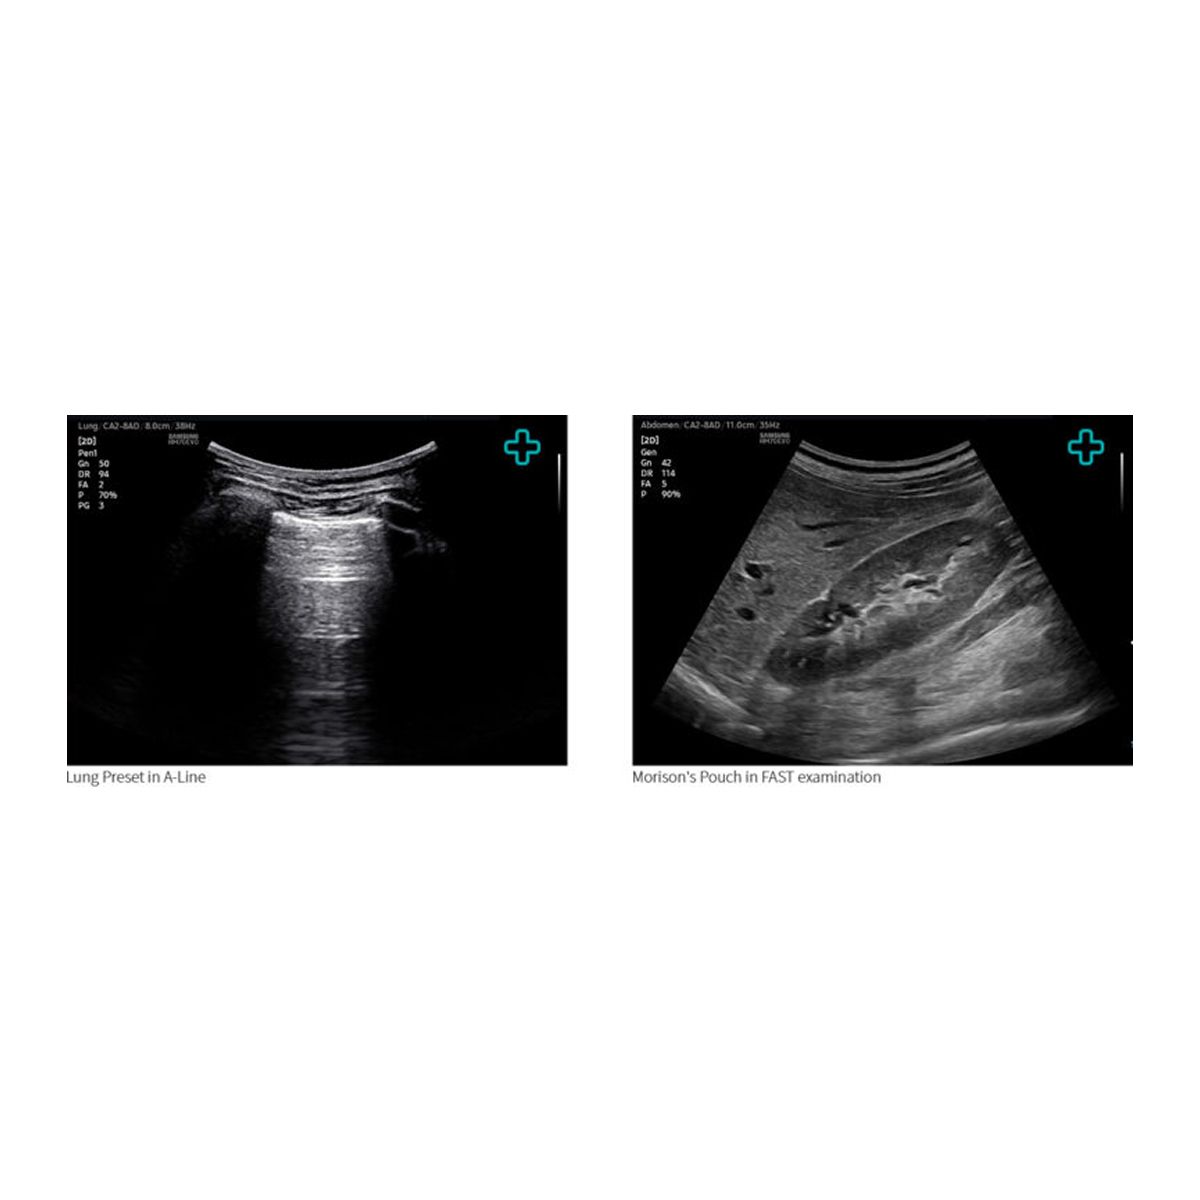

| Software/Licencias: | QuickExam, QuickSave, EzAssist, QuickPreset, EzExam+, NeedleMate+, NerveTrack, Lung preset y FAST preset. |